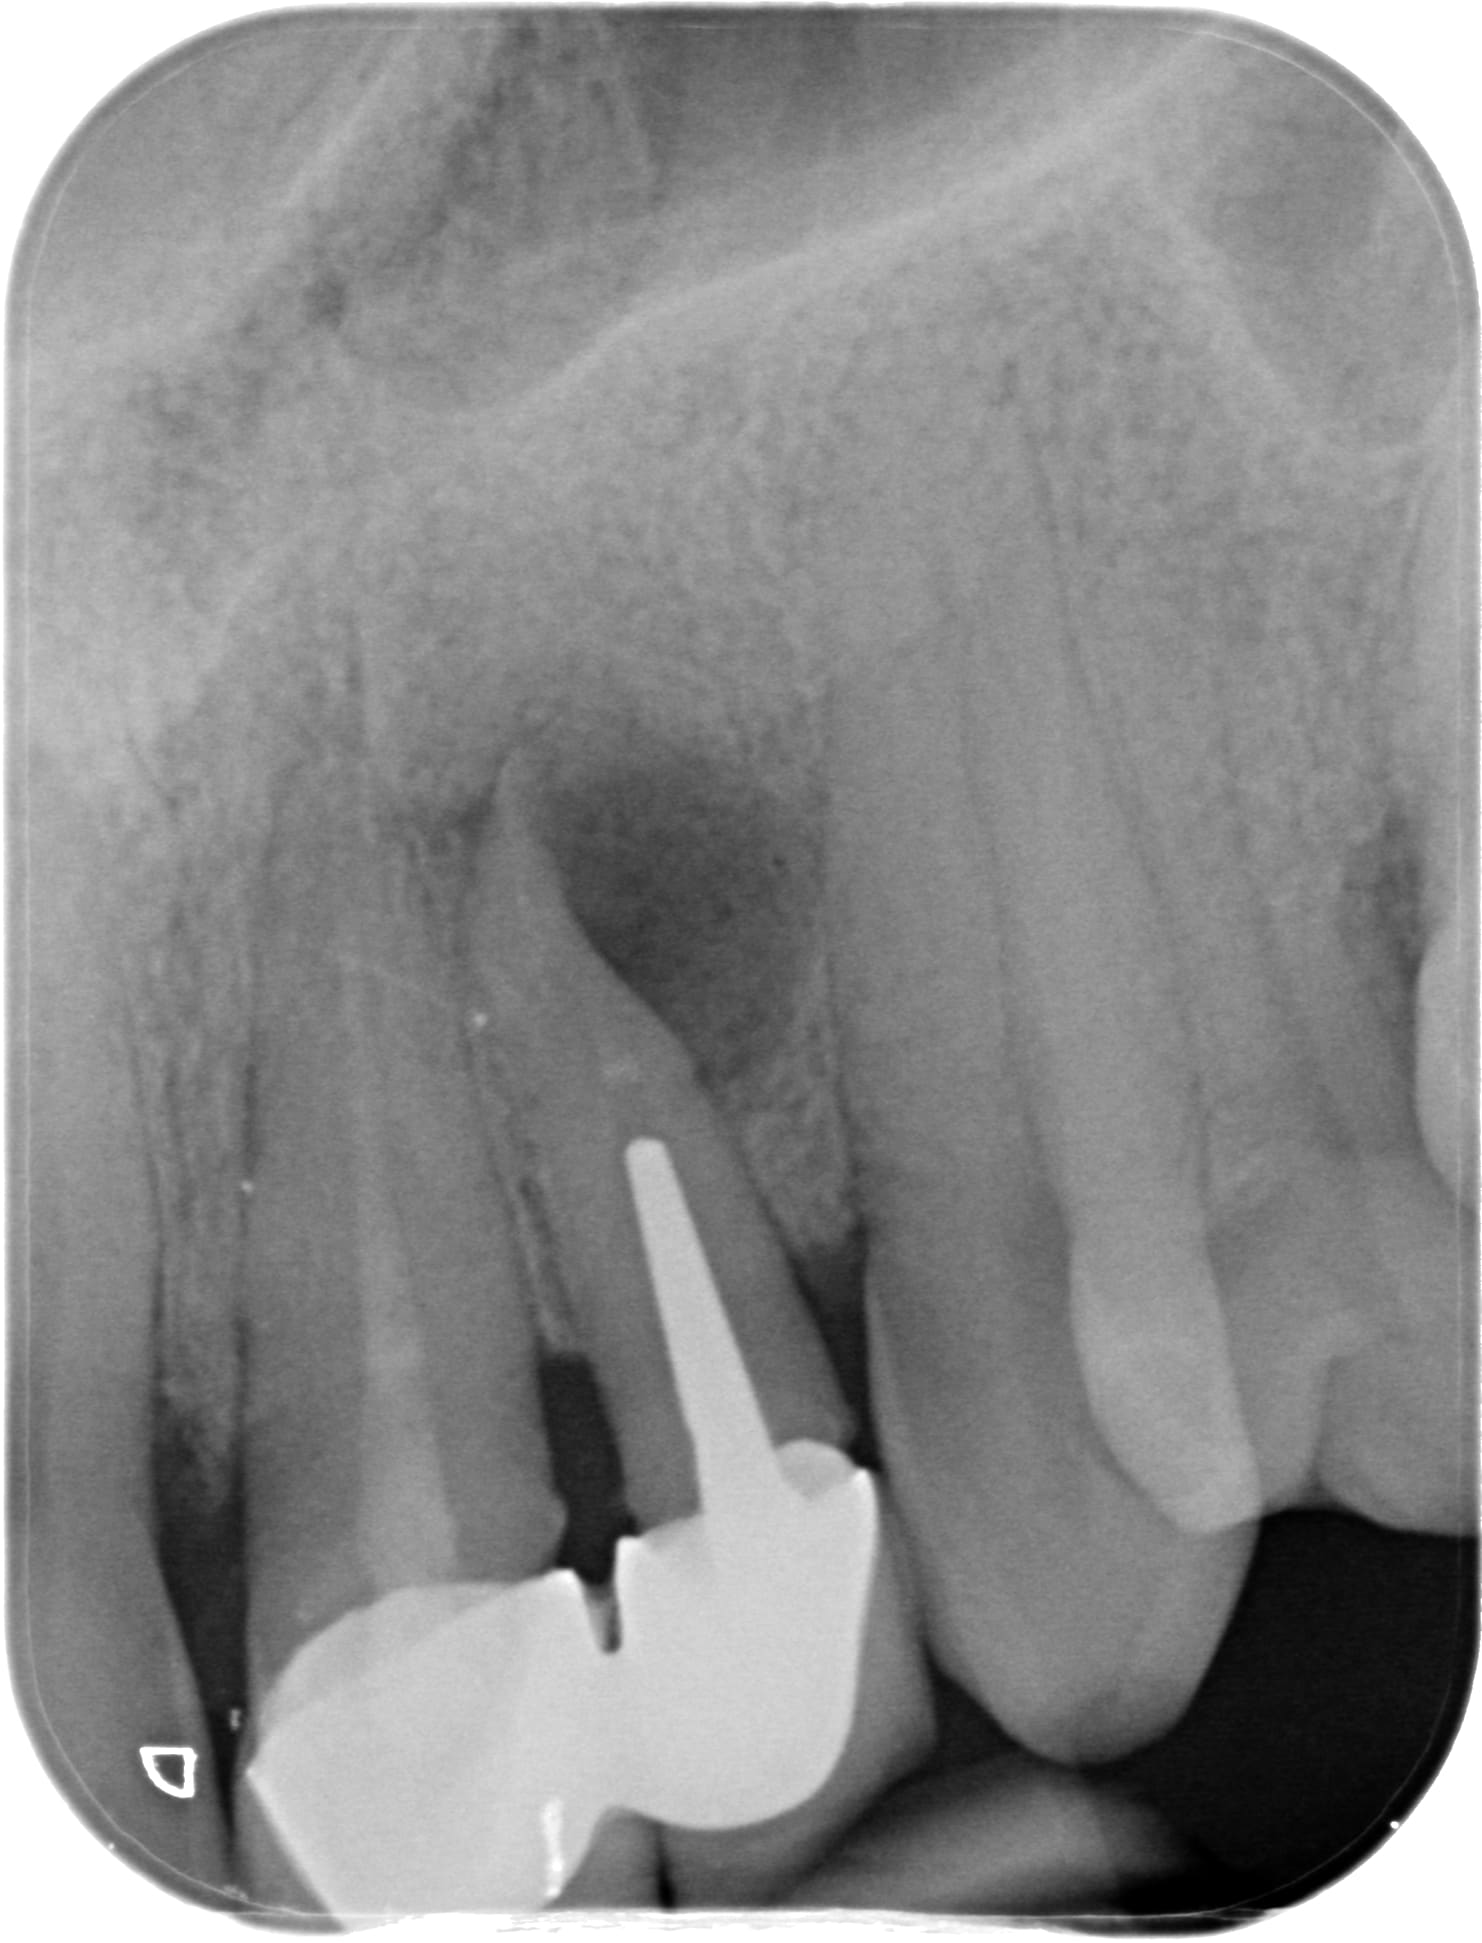

Apres la ce matin lui il va avoir du NPC mais pas sur tout... car médicalement justifié.

ca a 3 ans au passage.